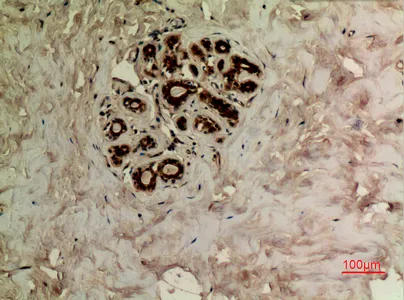

CD68 Rabbit Polyclonal Antibody

Cat: APRab08436